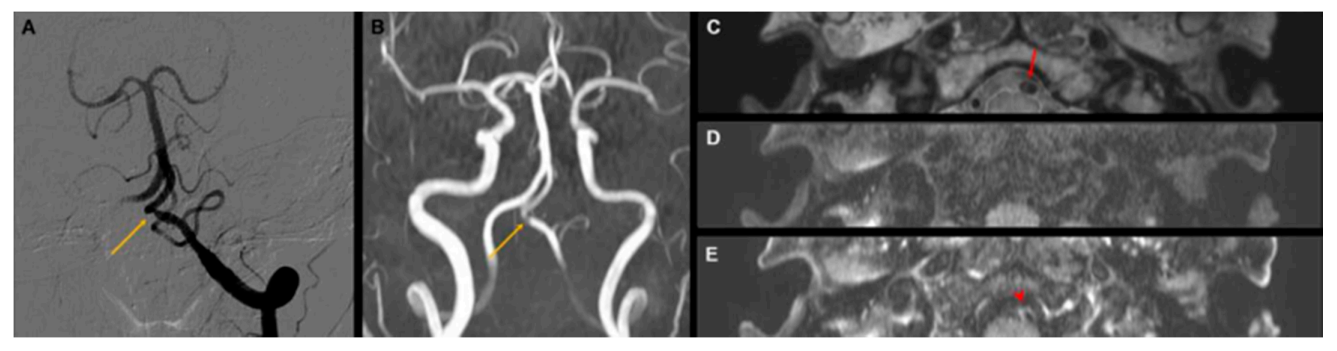

| Angiographic finding | ||

| Fusiform dilatation | 12 (44.4%) | 11 (40.7%) |

| Pearl–string sign | 16 (59.2%) | 16 (59.2%) |

| Dissection sign | ||

| Double-lumen sign or intimal flap | 21 (77.7%) | 6 (22.2%) |

| Intramural hematoma | 20 (74.0%) | Not evaluated |